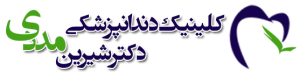

ایمپلنت پانچ، که به آن ایمپلنت فوری، ایمپلنت بدون درد و خونریزی یا ایمپلنت فلپ لس هم میگویند، روشی نوین برای جایگزینی دندانهای از دست رفته است. این روش در مقایسه با روش سنتی ایمپلنت، که نیاز به جراحی و برش لثه دارد، مزایای بیشتری دارد. در این روش، لثه به طور کامل کنار زده نمیشود و فقط با استفاده از ابزارهای ظریف، سوراخی کوچک در لثه ایجاد شده و ایمپلنت مستقیماً در استخوان فک قرار داده میشود.

ایجاد سوراخ: با استفاده از ابزارهای ظریف، سوراخی کوچک در لثه ایجاد میشود.

قرار دادن ایمپلنت: ایمپلنت به طور مستقیم در استخوان فک قرار داده میشود.